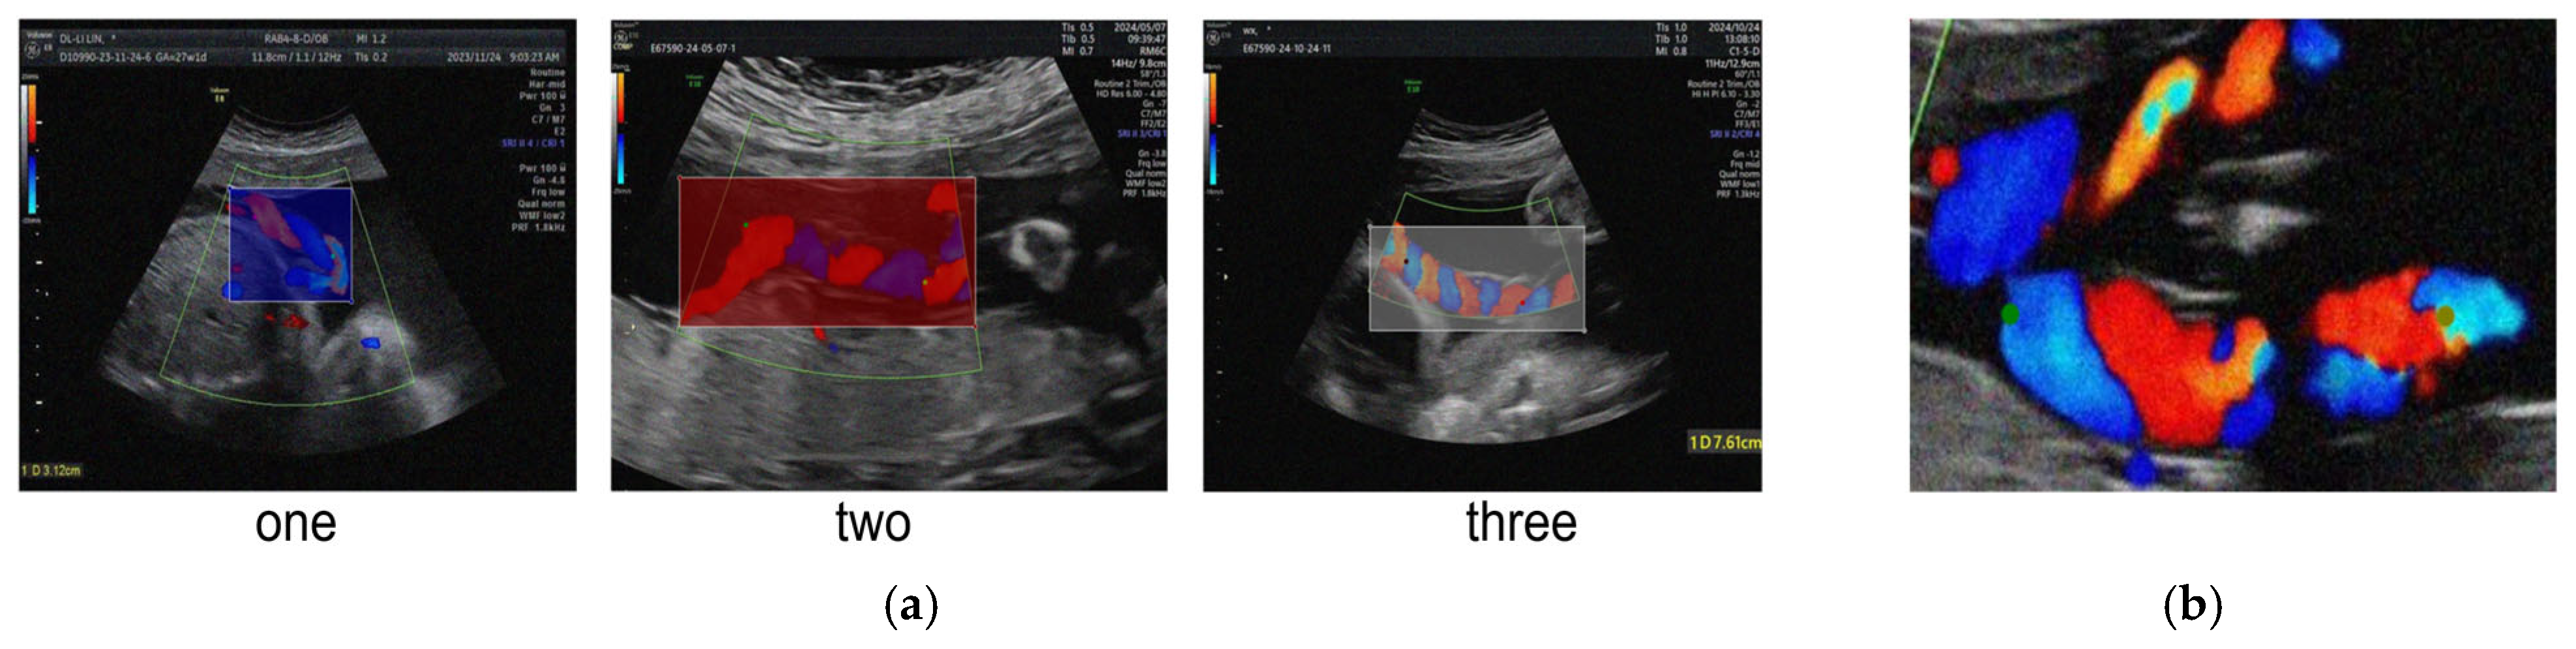

We performed data annotation using the LabelMe tool, encompassing two tasks: object detection and keypoint detection. As illustrated in Figure 6a, for the object detection task, experienced clinicians annotated the number of umbilical cord coils in the ultrasound images, categorized into three classes: “one,” “two,” and “three,” corresponding to 1, 2, and 3 coils, respectively. After annotation, the dataset contained 612, 1004, and 402 instances for each class. For the keypoint detection task, as shown in Figure 6b, ultrasound specialists labeled key anatomical landmarks of the umbilical cord following standardized annotation protocols to facilitate subsequent calculation of the coiling index. For training and validation, the dataset was randomly split at a 7:2:1 ratio into training (1412 images), validation (403 images), and test (203 images) sets. The splitting strictly followed the subject-exclusive principle, ensuring that images from the same subject did not appear across different subsets, thereby preventing data leakage and enhancing external validity.

Figure 6. Examples from the UCI Dataset. (a) Object detection labels, (b) Keypoint detection labels.